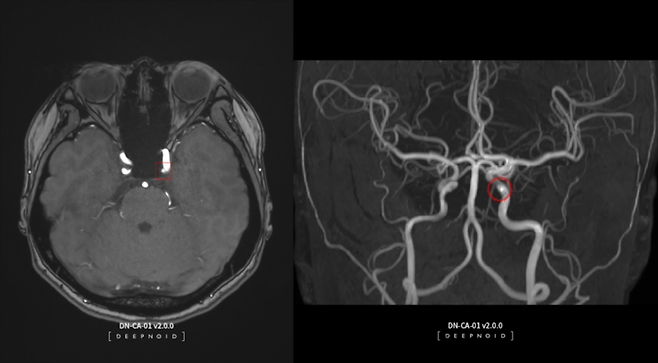

2008년 의료 AI 전문 기업으로 시작한 딥노이드는 의료 분야를 넘어 산업·보안 영역으로 사업 범위를 넓히고 있다. 2021년 코스닥 시장에 입성했다. 사업군은 크게 의료 AI와 산업 AI로 나뉜다. 이 중 대표 제품으로 뇌동맥류 AI 영상 판독 솔루션인 딥뉴로(DEEP:NEURO)와 딥러닝 기반 머신비전 솔루션인 딥팩토리(DEEP:FACTORY)가 있다. 딥노이드의 주력이기도 하다.

딥뉴로는 뇌혈관 MRA(자기공명혈관조영술) 영상에서 뇌동맥류 의심 부위를 AI로 판독·분석해 진단을 보조하는 진단 솔루션이다. 2017년 기준 국내 연간 뇌혈관질환 환자수는 약 92만명에서 2021년 110만명으로 급증했다. 손 본부장은 "매년 건강검진을 받는 사람이 있는 만큼 매출이 꾸준히 발생할 수 있을 것으로 본다"며 "확진을 받은 사람이 110만명이지만 검사를 받는 사람까지 포함하면 매출 규모는 예상 대비 더 커질 수 있을 것"이라고 설명했다.

딥뉴로의 매출은 올해 연말부터 발생할 것으로 예상된다. 최근 혁신의료기술로 선정되면서 한시적 비급여 대상으로 임상을 할 수 있게 됐다. 여기에 의료 AI 영상 판독 솔루션인 딥체스트(DEEP:CHEST), 딥렁(DEEP:LUNG), 딥스파인(DEEP:SPINE) 3종 모두 건강검진센터를 중심으로 공급한다는 계획이다.